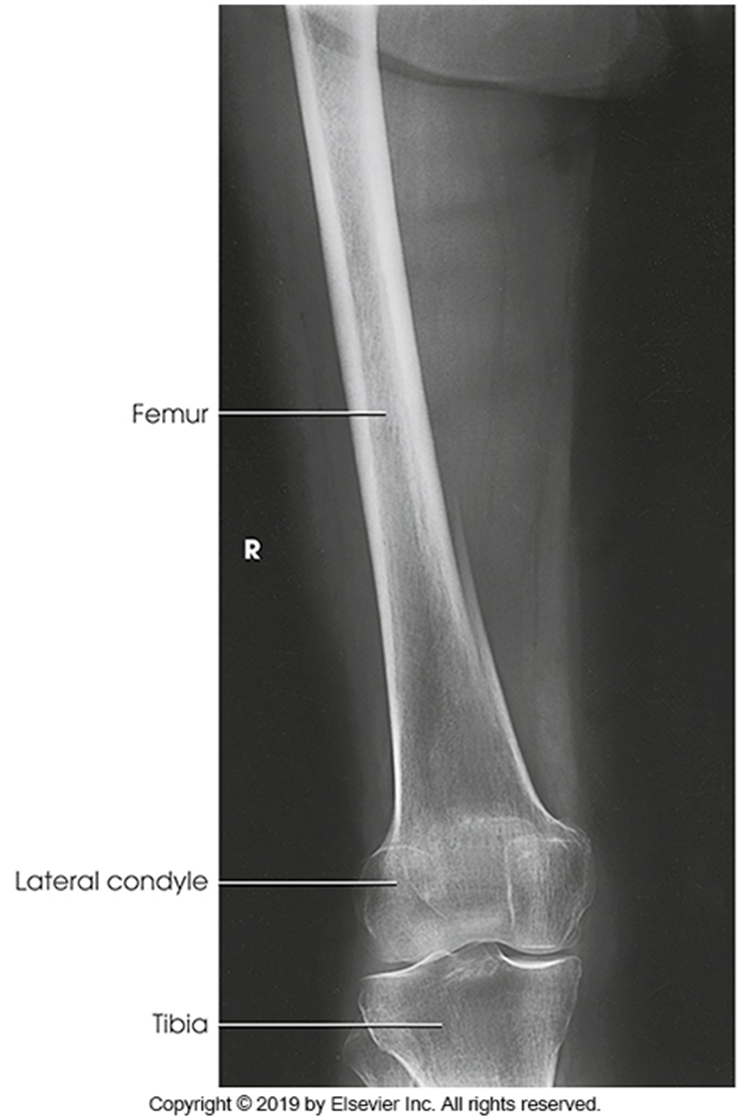

AP Femur

•Evidence of proper collimation and the presence of a side marker placed clear of the anatomy of interest

•Most of the femur and the joint nearest to the pathologic condition or site of injury (a second projection of the other joint is recommended)

•Femoral neck not foreshortened on the proximal femur

•Lesser trochanter not seen beyond the medial border of the femur or only a very small portion seen on the proximal femur

•No knee rotation on the distal femur

•Gonad shielding when indicated, but without the shield not covering proximal femur

•Any orthopedic appliance in its entirety

•Bony trabecular detail and surrounding soft tissues

Lesser trochanter is on, leg is not rotated in, under-rotated, hanging out too laterally

Leg was not internally rotated

No repeat, lesser trochanter can hardly see

Missing anatomy

slight medial rotation